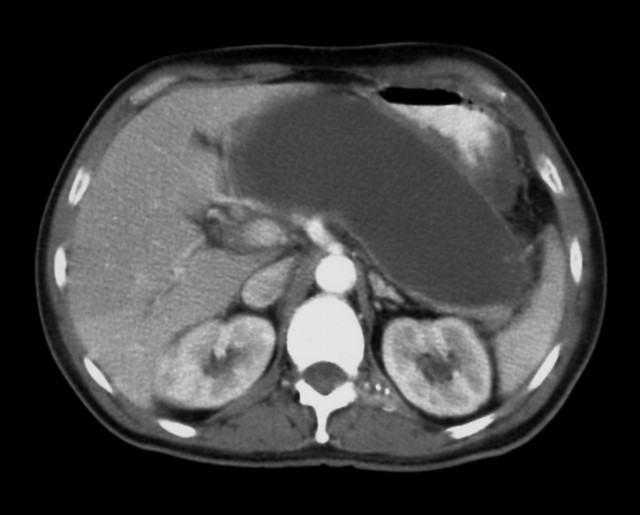

给大家分享一个患者病例,男,52岁,肝囊肿2.6 cm×1.8 cm, 肝硬化早期,肝实质回声增粗不均匀,来看诊的时候精神头特别差,脸色蜡黄,眼白也有点黄,说自己两肋胀得疼,尤其是生气之后,疼得更厉害,吃点东西就不消化,还总觉得浑身没力气。

调理了几个疗程,脸色红润了,眼白的黄气也退了,两肋不胀疼了,乏力、消化不良的问题也消失了。肝囊肿缩小到了1.5 cm×1.2 cm,肝实质回声也比之前均匀了,肝硬化的病情控制住了,没有往坏的方向发展。后面让患者用三叶配着煮水巩固调理。后期随访,患者身体没有出现明显不适。